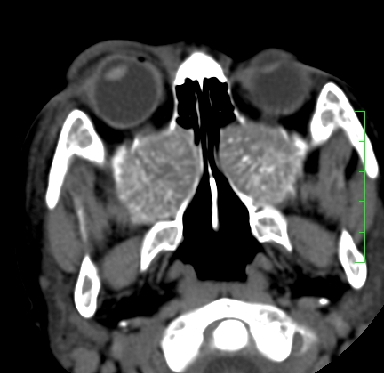

标题: PED1889:上颌窦病变

m,10y,外伤做ct

骨化性纤维瘤可能性大。(与骨纤的鉴别:常见于面颅骨,多骨发病)